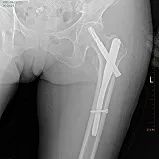

2、股骨粗隆間骨折

術(shù)前

髓內(nèi)釘固定術(shù)后